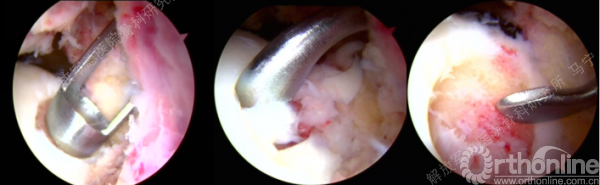

关节镜下所见软骨损伤,IV度损伤。

损伤软骨组织的清理(术中备了眼科器械,来辅助完成)。

损伤软骨组织的清理。